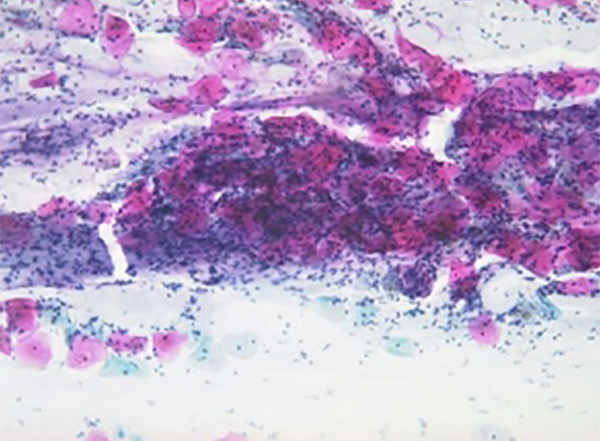

Dünnschichtzytologie, Monolayer, Flüssigkeitszytologie

Schon der bisherige Krebsabstrich bringt ein hohes Mass an Sicherheit bei der Früherkennung der Vorstadien des Gebärmutterhalskrebses. Es sind technische Gründe, die bei diesem Verfahren einen kleinen Prozentsatz an Unsicherheit übrig lassen.

Ein neues und aufwändiges Verfahren des Vorsorge-abstriches kann dieses Risiko noch weiter reduzieren. Das Verfahren wurde in den USA entwickelt und steht jetzt auch hier zur Verfügung.

Dabei wird aus dem Gebärmutterhals Zellmaterial gewonnen und automatisiert nach im Dünnschicht-